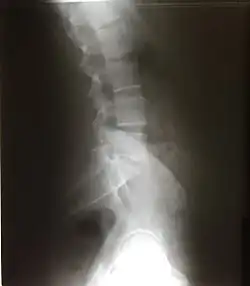

Scalloping vertebrae is the increase in the concavity of the posterior vertebral body. It can be seen on lateral X-ray and sagittal views of CT and MRI scans. Its concavity is due to the increased pressure exerting on the vertebrae due to a mass. Internal spinal mass such as spinal astrocytoma, ependymoma, schwannoma, neurofibroma, and achondroplasia causes vertebrae scalloping.[20]

Excessive or abnormal spinal curvature is classed as a spinal disease or dorsopathy and includes the following abnormal curvatures:

- Kyphosis is an exaggerated kyphotic (convex) curvature of the thoracic region in the sagittal plane, also called hyperkyphosis. This produces the so-called "humpback" or "dowager's hump", a condition commonly resulting from osteoporosis.

- Lordosis is an exaggerated lordotic (concave) curvature of the lumbar region in the sagittal plane, is known as lumbar hyperlordosis and also as "swayback". Temporary lordosis is common during pregnancy.

- Scoliosis, lateral curvature, is the most common abnormal curvature, occurring in 0.5% of the population. It is more common among females and may result from unequal growth of the two sides of one or more vertebrae,[21][22] so that they do not fuse properly. It can also be caused by pulmonary atelectasis (partial or complete deflation of one or more lobes of the lungs) as observed in asthma or pneumothorax.

- Kyphoscoliosis, a combination of kyphosis and scoliosis.